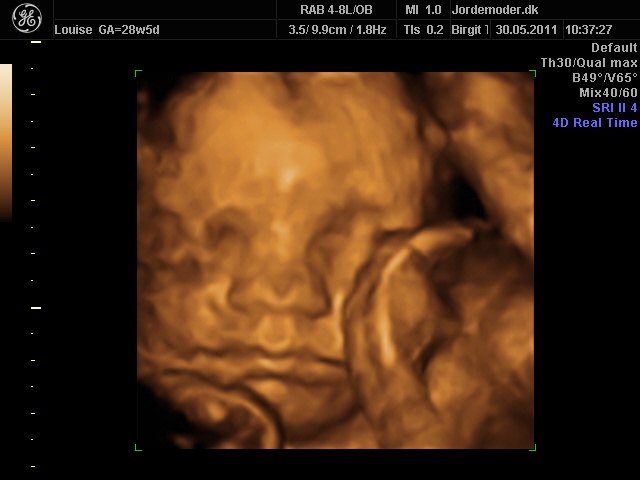

i uge 28

Vedhæftede fotos (klik for at se i fuld størrelse)